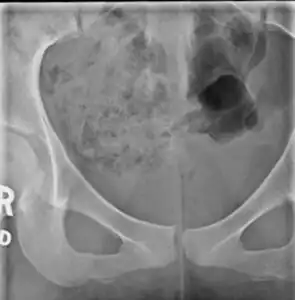

X-ray -

Lateral radiograph showing a fracture of the coccyx, as well as a lower lumbar fracture